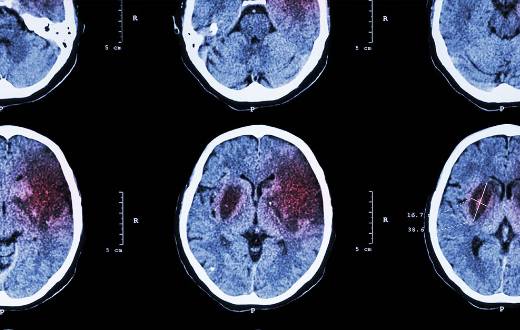

Aunque los datos ofrecidos por el INE incluyen estadísticas de muchos grupos de enfermedades, si solo tenemos en cuenta enfermedades concretas, una enfermedad neurológica, el ictus, es -tras la insuficiencia cardiaca y la neumonía-, la tercera enfermedad que más ingresos hospitalarios generó en el último año en España: 106.641 personas fueron ingresadas por este motivo.

Además, el ictus es, tras la esquizofrenia, la segunda enfermedad que más número de días de ingreso requirió en los hospitales españoles: en el último año supuso un total de 1.439.961 estancias. Por otra parte, otra enfermedad neurológica, la demencia, es la segunda enfermedad que más media de días de ingreso requiere en España, con 50,3 días de estancia media.

Asimismo, aunque no figuran entre los tres primeros puestos, otras enfermedades neurológicas como los traumas cerebrales, la epilepsia o la esclerosis múltiple, también se encuentran entre las enfermedades que demandan más recursos hospitalarios. Los traumas cerebrales (40.3745 personas en el último año) y la epilepsia (19.715 pacientes) son las entidades que, tras el ictus, ocupan el segundo y tercer lugar como principales causas de hospitalización neurológica. La demencia (con 427.636 estancias), seguidas de los traumas cerebrales (331.918) y de ingresos por epilepsia (124.245), son tras el ictus las enfermedades neurológicas que supusieron un mayor número de estancias hospitalarias en el último año.